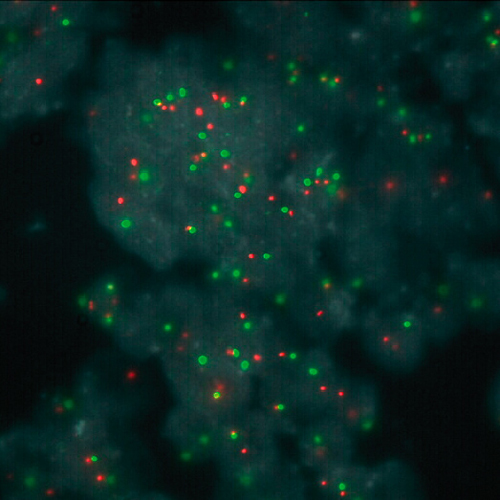

KBI-10503

1q21 / 8p21